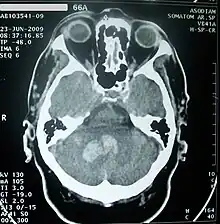

Imagerie cérébrale

Elle permet de voir l'accident vasculaire, de le dater en partie, d'en connaître le mécanisme, d'éliminer d'autres maladies pouvant être responsable de l'accident déficitaire.

Le scanner crânien est fait, sauf contre-indication, avec injection d'un produit de contraste iodé. Si l'accident est ischémique, il permet de visualiser la topographie, l'étendue et le nombre de lésions. S'il est hémorragique, il en fait le diagnostic.

L'imagerie par résonance magnétique crânienne, faite également après injection d'un produit de contraste, donne le même type de renseignements mais est plus sensible si l'accident est très récent. Elle peut être complétée dans la même séance par une angio-IRM permettant de visualiser les grands axes vasculaires extra et intracrâniens.